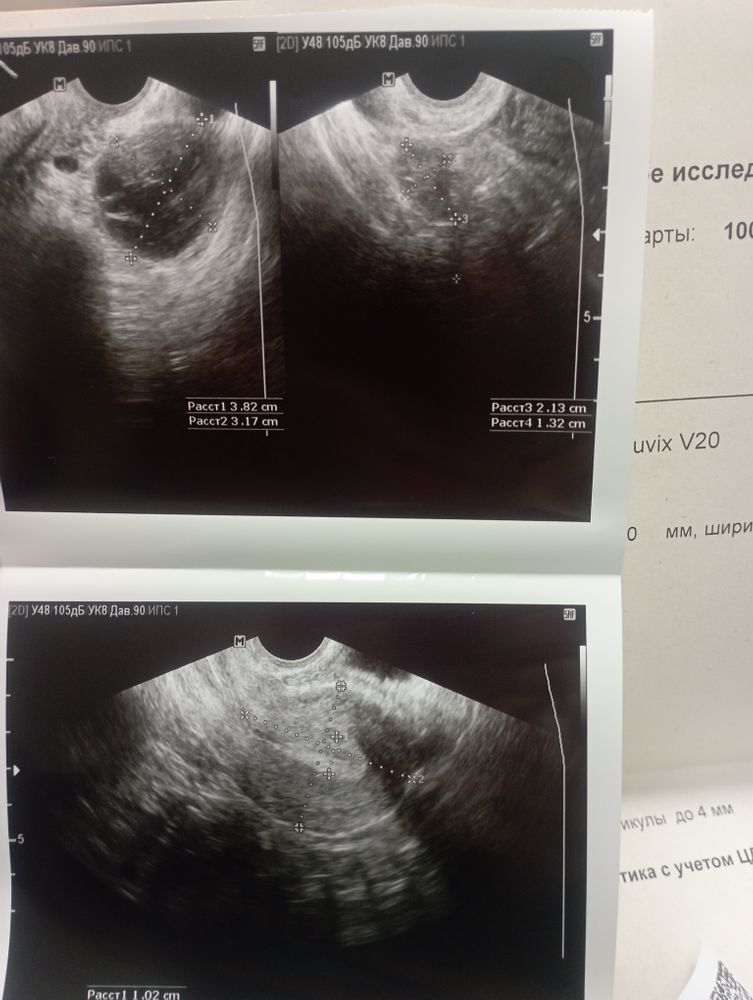

Делала УЗИ в первой фазе. Всё было ок. Врач смотрит и говорит - не знала бы, что у вас в первой фазе все хорошо, подумала бы - киста. Ну значит это жёлтое тело и в заключении жёлтое тело под вопросом. Как так?

И мне сказала, что жидкости в позадиматочном пространства мало. А в заключении написала, что вообще нет.

Я ещё сдавала прогестерон -60. Не понимаю - овуляции что, могло и не быть?

Ещё сказала, что в правом есть фолликул 7мм, но не написала. Или я что-то не так поняла.

Прогестерон хороший для нормального овуляторного цикла, эндометрий норм. Судя по анализу, овуляция была. Но вот как не отличили жёлтое тело от кисты, непонятно. Там достаточно посмотреть кровотоки

Фотографии и описание несколько противоречивы.

Впрочем, по узи не всегда можно разглядеть киста это или жёлтое тело.

Рискну предположить, что киста, тк. Прогестерона много и второй яичник маленького объёма (если обычно правый яичник у вас больше 3) .

Размеры не большие. Даже если и киста, то скорей всего, сама рассосется